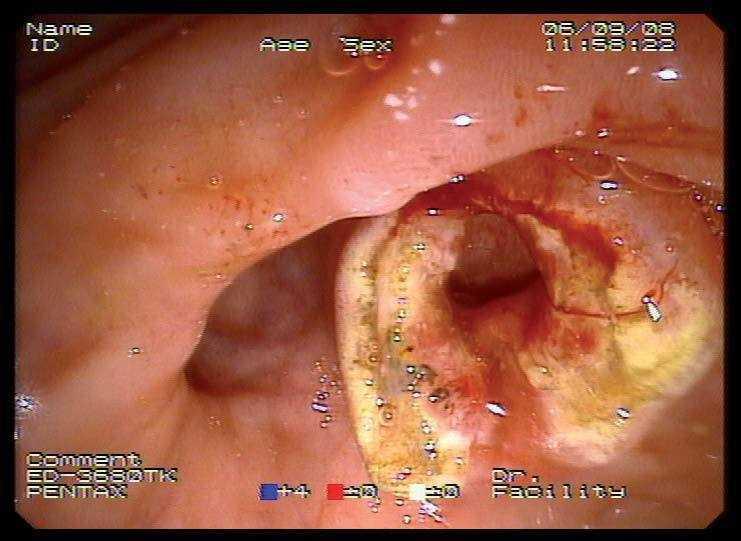

Mujer de 87 años que ingresa en el servicio de cirugía por ictericia, colangitis y pancreatitis aguda. Se instauró tratamiento con sueroterapia y antibióticos, que consiguió la estabilización hemodinámica de la paciente. En una colangiopancreatografía por resonancia magnética (fig. 1) se observó un defecto de repleción en el colédoco distal. Con la intención de desobstruir la vía biliar, se realizó una colangiopancreatografía retrógrada endoscópica (CPRE), empleando sedación consciente con midazolam y dolantina. En la endoscopia, la ampolla de Vater se encontró muy abultada, con un orificio en el que parecía entreverse una coledocolitiasis (fig. 2). Se realizó una esfinterotomía biliar amplia (fig. 3) y se extrajo una coledocolitiasis de 13 mm de diámetro máximo, que estaba impactada en la ampolla (fig. 4). La evolución de la paciente fue satisfactoria.

Fig. 1